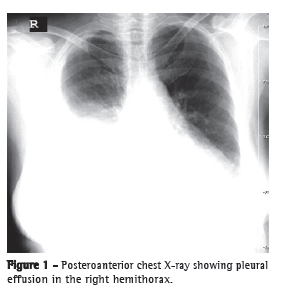

A chest X-ray demonstrated significant right-sided pleural effusion (Figure 1), and a CT scan of the chest revealed right pleural effusion, thin septa, and atelectasis of the underlying lung (Figure 2). Serum levels of urea and creatinine were 132 mg/dL and 3.9 mg/dL, respectively. Because the respiratory distress developed suddenly and soon after percutaneous nephrolithotomy, urinothorax was suspected. The diagnosis was confirmed after thoracocentesis, which yielded approximately 1,100 mL of pleural fluid, with a ratio between the creatinine content in pleural fluid and that in serum of 1.78 (normal, < 1). A 28 Fr chest tube was inserted into the right fifth intercostal space in order to drain the effusion.